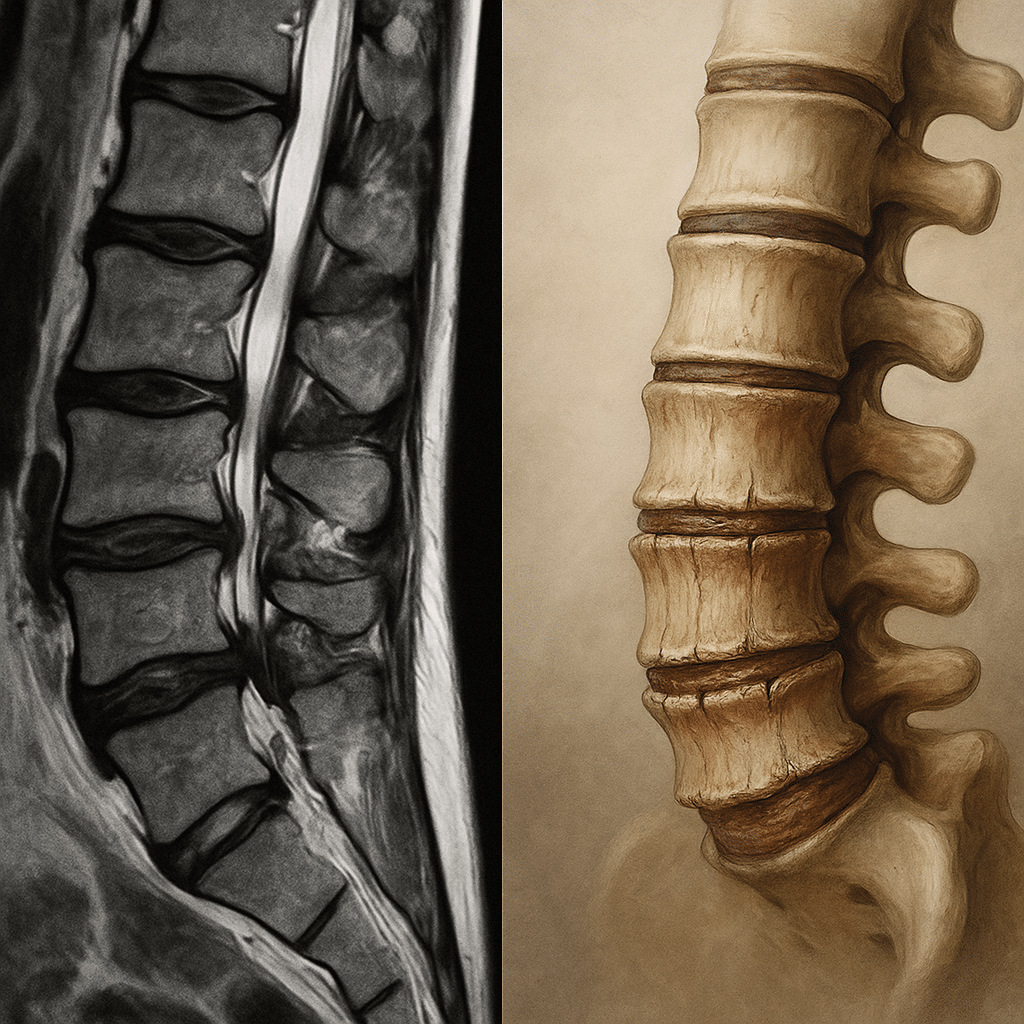

La columna vertebral es una de las estructuras más sofisticadas de nuestro cuerpo. Sus discos intervertebrales son como amortiguadores: absorben impactos y nos permiten movernos con flexibilidad.

Cada disco está formado por:

· Núcleo pulposo (NP): un gel rico en agua y proteoglicanos que da elasticidad.

· Anillo fibroso (AF): un aro resistente que lo envuelve y protege.

· Placas terminales cartilaginosas (CEPs): que lo unen a las vértebras.

Cuando el agua y los proteoglicanos disminuyen, el anillo se daña y las placas se calcifican. El resultado es un disco menos flexible, más rígido y más vulnerable al dolor.